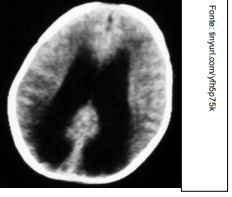

Um médico está atendendo Laura, estudante que retorna às aulas após internação recente em UTI por acidente vascular cerebral (AVC). No relatório de alta, consta que ela apresentou AVC tipo Hemorragia Subaracnoide Aneurismática, e há uma cópia da tomografia computadorizada de crânio, sem contraste, realizada pela paciente na admissão. A imagem que melhor corresponde ao achado do exame de imagem de Laura é: